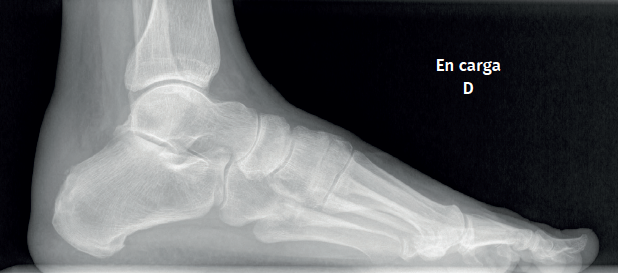

Approximately 6% of the general population will experience some pain episode of the Achilles tendon during life(1). Of these patients, approximately one-third will present tendon insertion damage(2,3). Patients with insertional tendinopathy of the Achilles tendon (ITA) typically experience pain and functional limitation, aggravated by physical activity and following resting periods. They may present thickening of the insertional portion of the tendon, most often at the lateral margin (Figure 1).

Figure 1. Insertional tendinopathy of the Achilles tendon. Thickening of the soft tissues, prominence on the external side.